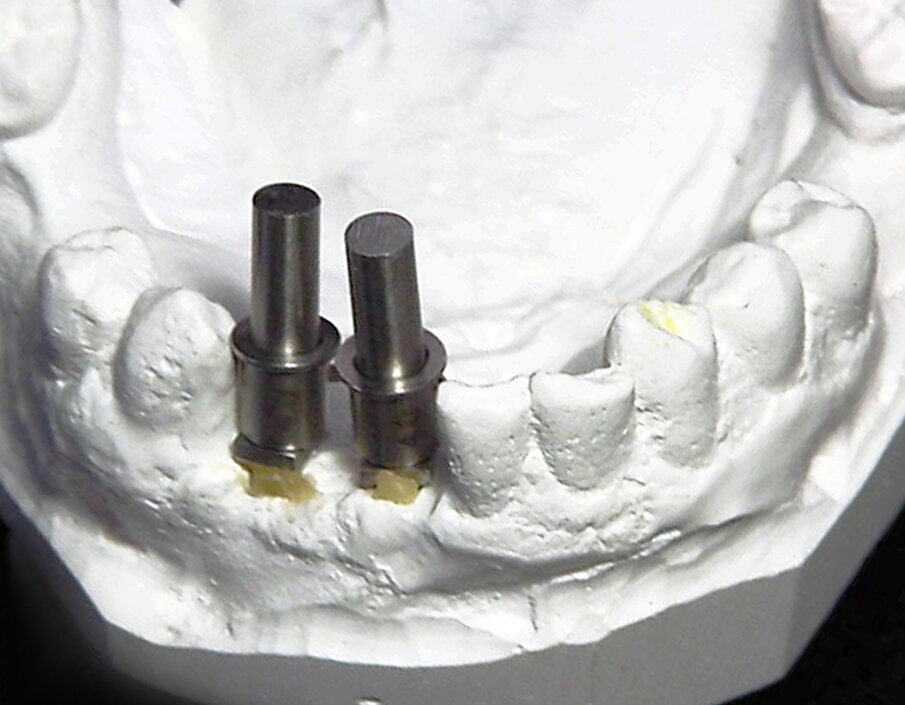

Figs. 8a & b: Corrected 1.0 mm offset guide posts with 3.9 mm upper parts for alignment of 4.0 mm guide sleeves placed into the post holes on the cast.

Fig. 9: Guide sleeves were placed on the upper removable parts of the corrected guide posts.